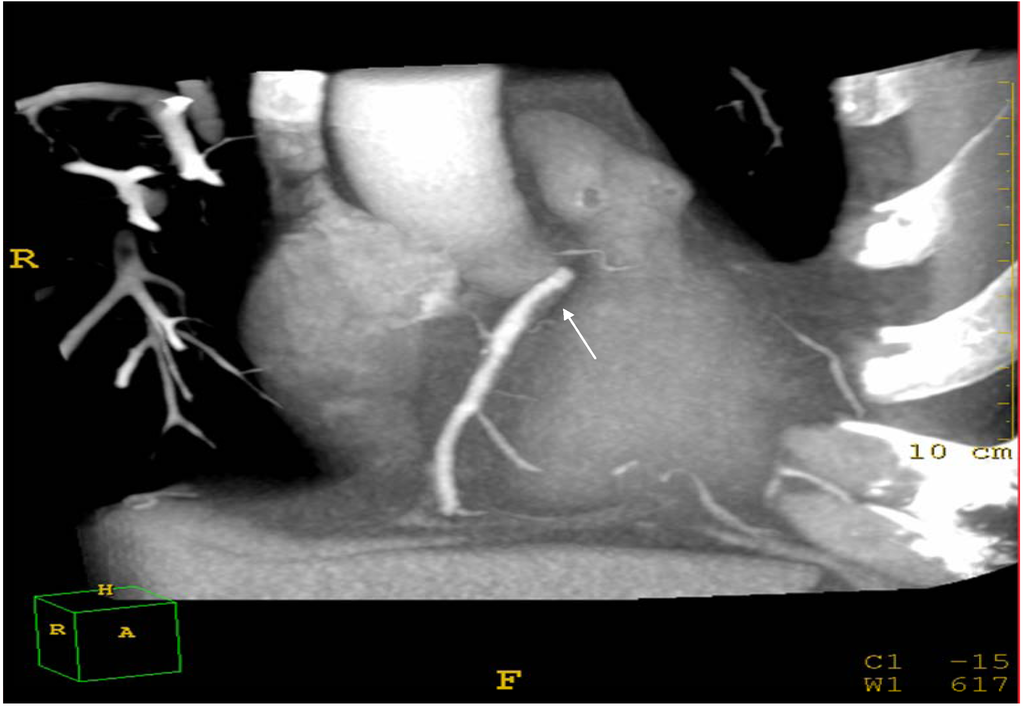

| Coronary artery disease (stenosis > 50%) | 30% | 15% | 0.001 |

| Coronary Plaques%Soft Plaques | 70%50% | 30%30% | 0.010.01 |